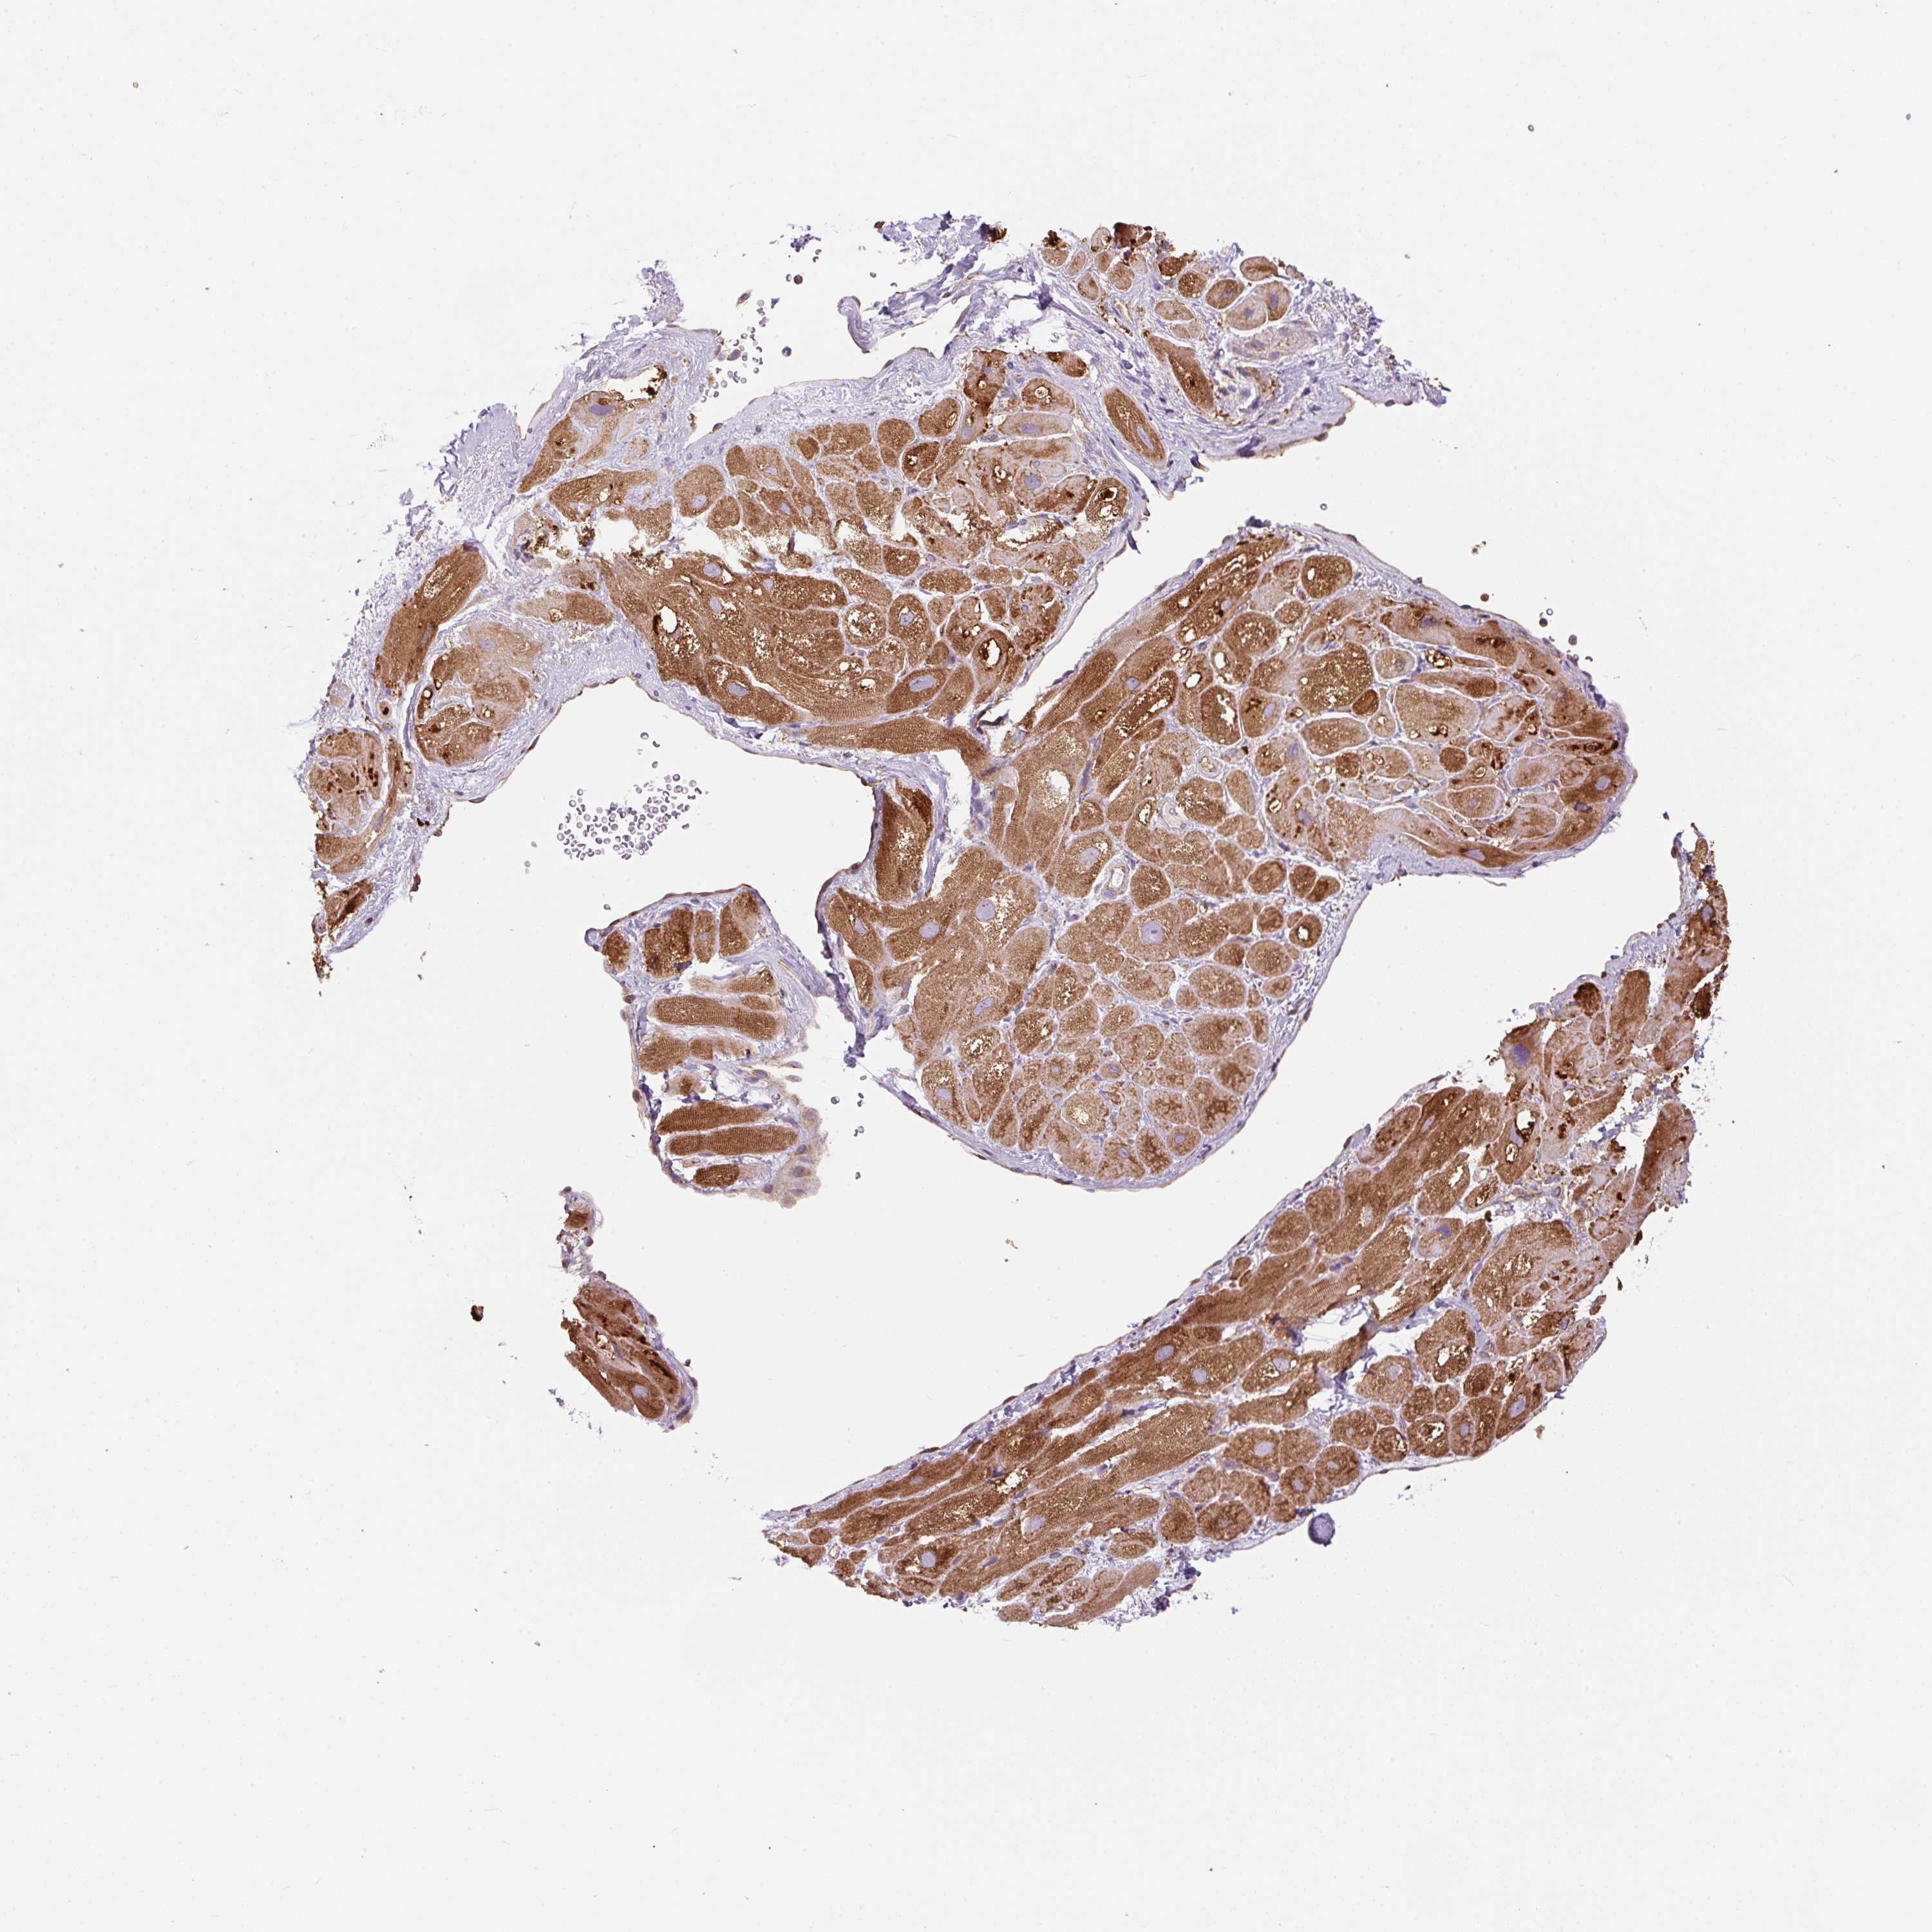

HEART MUSCLE - Antibody stainingi

Antibody staining in the annotated cell types in the current human tissue is reported as not detected, low, medium, or high, based on conventional immunohistochemistry profiling in selected tissues. This score is based on the combination of the staining intensity and fraction of stained cells.

Each image is clickable and will lead to virtual microscopy that enables deeper exploration of all samples and also displays staining intensity scores, fraction scores and subcellular localization as well as patient and tissue information for each sample.

Antibody HPA043900Antibody CAB004541

Cardiomyocytes HighNot detected